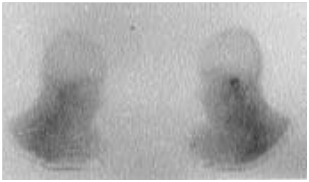

Figure 3 The left temporal bone shows an increased absorption of 67Ga (arrow).

The MEO is an otological infection that has life-threatening complications. It is considered as a complication of external otitis.2 Occurs mainly in the elderly who have diabetes or another condition that compromises the immune system. Doctors must be able to recognize this infection, initiate treatment, and refer patients to an Otolaryngologist. The precise etiology of this condition is unknown, but theories related to impaired immunity, the local tissue microangiopathie and even modified biochemistry of earwax have been proposed. Infection of the soft tissues of the external ear canal is common, especially in hot and humid climates. The usual triggers are trauma (often caused by q-tips) and exposure to the pool of water. The most frequently found germ is Pseudomonas aeruginosa, is not a normal germ of the EEC.3 Other possible germs include Staphylococcus epidermidis,4 gram negative bacteria and fungi. External otitis patients complain of earache and sensitivity to atrial movement. The otorrhoea may be present, the obliteration of the external ear canal by edema and secretions can cause hearing loss, or a feeling of fullness in the ear. The disease comes from the EEC and propagates through the osteo-cartilaginous junction to involve soft tissue under the temporal bone. Granulation tissue is usually present in the EEC. The spread of the infection can cause thrombosis of the lateral sinuses and petrous sinus upper and lower. Initially, the progressive skull base osteomyelitis can cause cranial Polyneuropathy, paralysis of the facial nerve being the most common; cranial nerves IX, X, and XI (the jugular foramen syndrome) nerves and cranial nerve XII (hypoglosse channel) are less often involved with the development of the sphenoidal sinusitis. Imaging to show the extension of the infection to the bony structures is usually required to establish the diagnosis of MEO6 imaging modalities include tomographic (CT) scan, scan bone to the technetium Tc99m medronate methylene diphosphonate, and scintigraphy to Ga 67 gallium citrate. CT is used to determine the location and extent of diseased tissue (Figure 1 & Figure 2). The temporal bone is the first os to be affected, with an imminent involvement of petrous apex and the mastoid process. Extratemporal extension has become rare since the introduction of powerful antibiotics. In evaluating the scanner, it is important to remember that at least one third of the minerals is lost before the radiological changes are becoming apparent; Conversely, the bone remineralization continued long after that infection is Gueriela scan is a diagnostic sensiblemais non-specific to the MEO, if to the 67Ga scintigraphy is available, (Figure 3). It must be used for the initial diagnosis and follow-up tool.7 Using in combination imaging modalities, it is possible to prove that the temporal bone is reached (scan and bone scan to the 99mTc) with infectious process (Ga 67 scintigraphy).6 MRI is of interest in advanced forms allowing a better analysis of the deep spaces of the face, the nervous foramina, merien hard spaces and the Medullary bone in the base of the skull.

The standardization of scintigraphy has a predictivede healing value. The treatment is based on antibiotic therapy extended replacing more surgical treatment. Is followed by CT to assess the decline in inflammatory lesions of the deep spaces of the face and bone necrosis. A strict control of diabetes mellitus is mandatory, although it may be difficult to achieve during the acute illness. Other immunosuppressants and comorbid States must also be managed effectively. Local treatment of the ear canal includes the cleaning and debridement more topical application of antimicrobial agents (antibiotics and other). Escrow and other necrotic tissues must be removed. Hyperbaric oxygen, an adjuvant to antibiotic therapy, supposed to increase the capacity of the cells polymorphonucleaires against pathogenic bacteria.8 However, the complexity of administration often limits the use of hyperbaric oxygen therapy. The surgery has a defined but more limited role in the treatment of the Osteitis of the base of the skull. Although the sequestered bone and abscesses are treated surgically, a new expanded operation can be counterproductive because the healthy bone may be exposed to infection.6 The differential diagnosis is done essentially with a neoplastic origin and more rarely with pseudo tumor inflammatory, Wegener's Granulomatosis.9